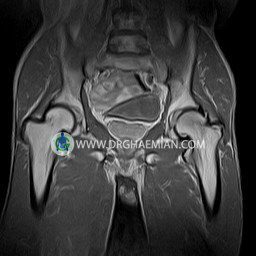

پزشکان اغلب از تصویربرداری ام آر آی برای تشخیص و درمان عارضه های پزشکی که فقط با استفاده از اشعه ایکس یا میدان مغناطیسی و امواج رادیویی قابل مشاهده است، استفاده می کنند. دستگاه ام آر آی تصاویر دقیق از ساختار های داخلی بدن ایجاد می کند. در این کیس استئومیلیت لگن، آتروز و سنیویت دیده می شود.

HIP JOINT MRI

( without contrast )

Technique : coronal STIR , coronal T2 , Axial T1 , axial T2 .

REPORT:

The femoral heads and acetabula are normal shape , signal intensity and the femoral heads are well covered by the acetabular margins .

The joint spaces are of normal width without fluid collection .

The articular surfaces are smooth and congruent and show normal cortical thickness .

Each femoral shaft has normal margins and contains a normal bone marrow signal .

The imaged muscles and the lesser pelvis show no abnormalities .

– Heterogeneous signal change (high T2/STIR , low T1) in proximal metaepiphysis of left femur without articular surface irregularity suggestive for bone bruise (stress fracture?), osteomyelitis & arthritis and marrow infiltration (less probable)

– Left hip joint effusion suggestive for synovitis

are seen.

COMMENT: Clinical correlation and MRI with contrast are recommended.